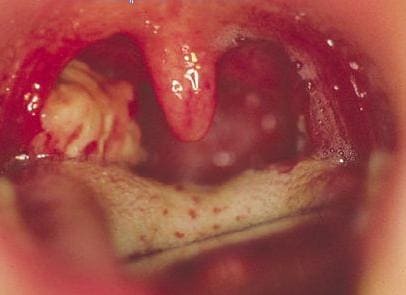

Боль в шее и лопатках может возникать при воспалительных заболеваниях лор – органов – ангина, фарингит, ларингит, трахеит, заглоточный абсцесс.

Фарингит

Температура, боли в горле, боли при глотании, изменение голоса, «заложенность» горла должны привести больного к ЛОР врачу. Острый отит может сопровождаться односторонними болями в шее.